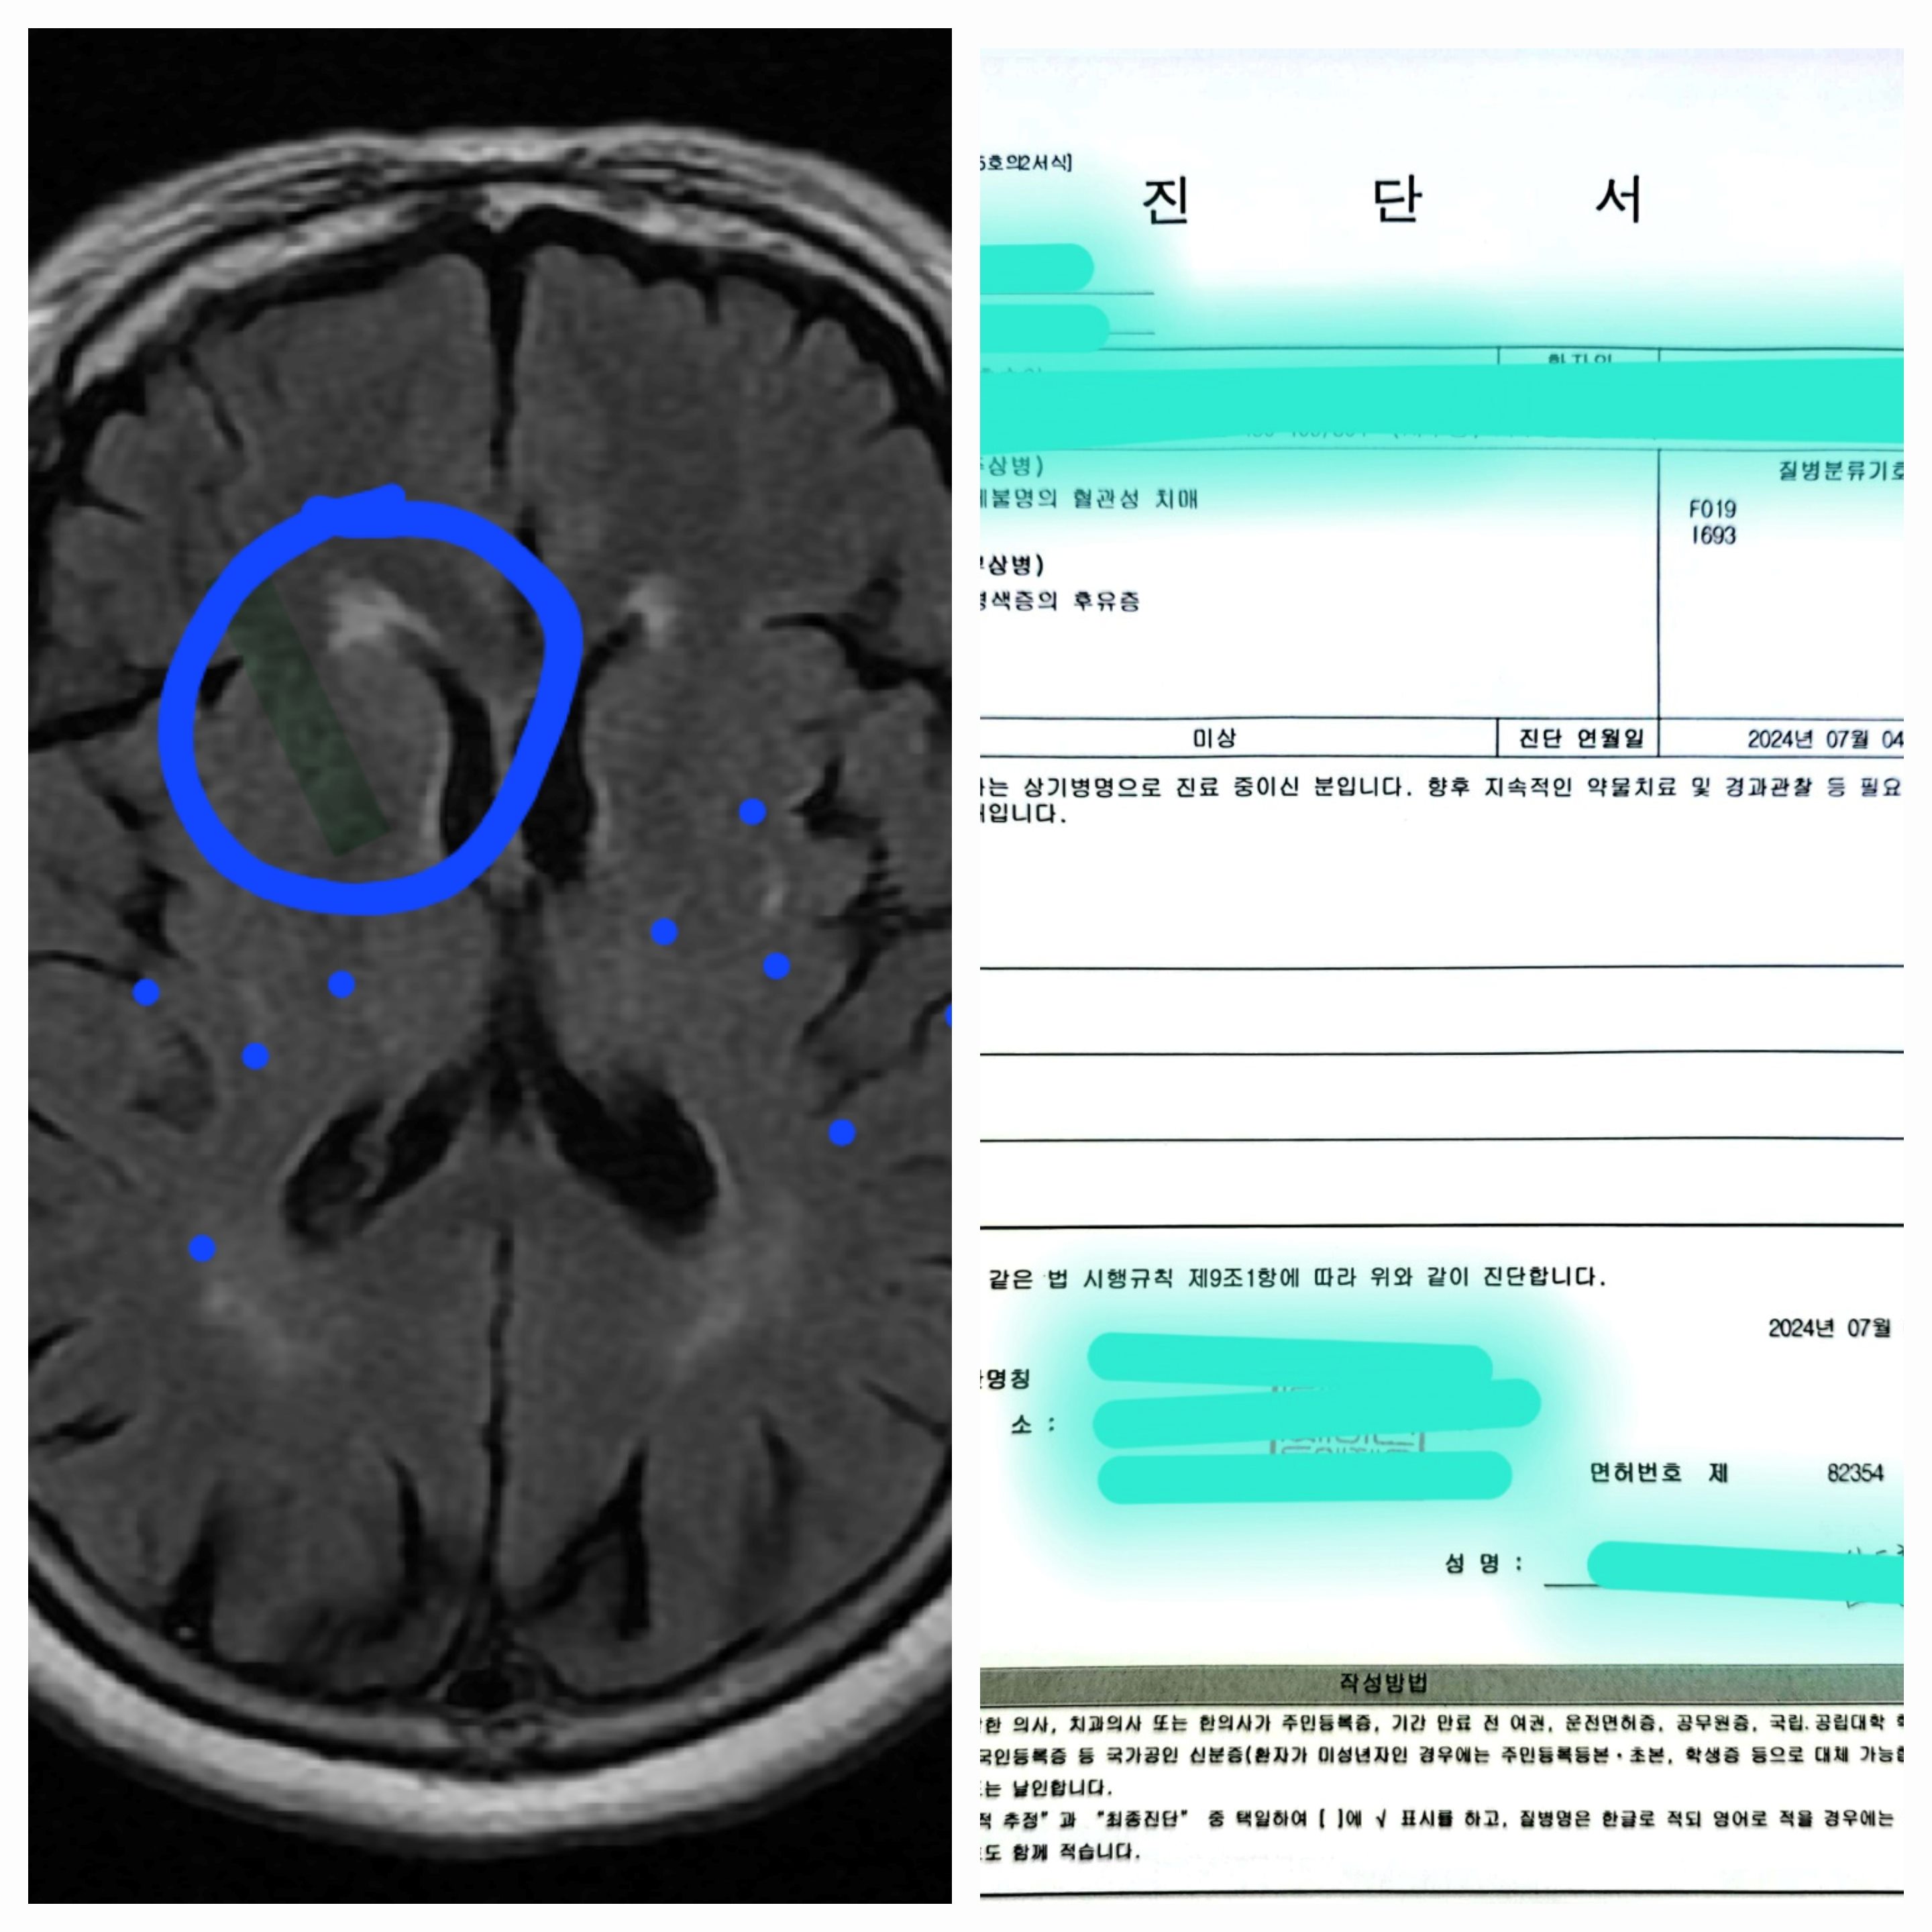

- 진단 결과: 상세 불명의 혈관성 치매, 뇌경색증의 후유증

- 치료 계획:

- 지속적인 약물 치료 및 경과 관찰: 리넥신서방정(혈전생성억제제) 1정, 뉴토인정5mg(알츠하이머형태의 치매증상완화제) 0.5정, 펙수클루정40mg(위산분비억제제) 1정이 1회 투약량이며, 총 1개월분 처방받았습니다. 원래 저녁 식후에 복용해야 하나, 수면 장애가 있는 사람은 아침 식후에 복용 가능합니다.

- 검사 및 진료 비용: 총 764,600원

- 3차 진료 비용: 본인부담금 7,200원+비급여 20,000원=27,200원(진찰료, 진단서발급비용)